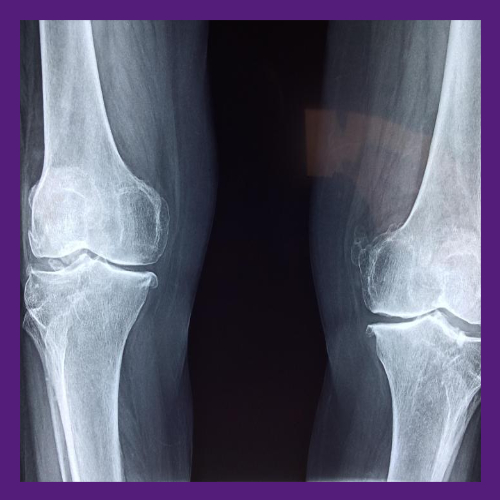

뼈 건강은 현대 사회에서 점점 더 많은 사람들이 고민하는 문제 중 하나예요. 특히 골다공증이나 뼈 약화로 인해 발생하는 통증과 불편함은 우리의 일상적인 삶의 질을 크게 저하시킬 수 있어요. 혹시 계단을 오르내릴 때 관절이 아프거나, 작은 충격에도 쉽게 골절되는 경험이 있진 않으셨나요? 이런 증상들은 모두 뼈 건강에 대한 적신호일 수 있어요.